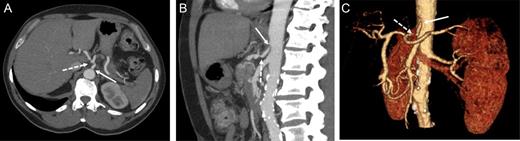

A 60-year-old male, with irrelevant medical history (no chronic disease or treatment), and complaining of recurrent abdominal pain, was referred for abdominal computed tomography (CT). Due to a suspicion of a mass in the pancreatic body (Fig. 1), the patient was referred to our hospital for re-evaluation and treatment. Physical examination was not remarkable, besides epigastric pain during deep palpation. All blood tests were within normal ranges. In re-evaluation of a previous CT, performed in a different hospital, our Radiological Department reported: ‘a malign appearing mass in the pancreatic corpus with extension to the pancreatic neck, with no invasion of the Superior Mesenteric Artery (SMA) and Superior Mesenteric Vein (SMV)’. Laparotomy was performed. Intraoperatively, a mass of ∼6–8 cm was discovered, located from the neck to the corpus of the pancreas. During exploration, the leading surgeon noticed that vascular structures, both the superior anterior pancreaticoduodenal artery (SAPDA) and the inferior anterior pancreaticoduodenal artery (IAPDA), which are collaterals between the gastroduodenal artery (GDA) and the SMA, were enlarged and tortuous. After the Kocher maneuver, all resections (jejunal, postpyloric gastric, common bile duct) were performed. Immediately after the GDA was clamped and cut, an ischemic appearance was seen on the liver and stomach. At this point, it came to mind that there was a total celiac trunk occlusion or possible MALS. To prevent ischemic hepatic injury, immediate re-anastomosis of the cut GDA was performed. After re-anastomosis was completed, a rapid change in the color of the liver and stomach was observed. And after re-anastomosis of the GDA, digital palpation and Doppler ultrasonography revealed that circulation of the common hepatic artery, splenic artery and left gastric artery was restored, and all these vascular circulations were from the SMA via the GDA.

Preoperative computer tomography, mass (arrow) located in corpus of the pancreas.

Contrast-enhanced CT in the arterial phase: axial (A) and sagittal (B) maximum intensity projections (MIP), and coronal oblique 3D volume-rendered (VR) images (C) demonstrating proximal celiac artery narrowing (arrow) due to compression by the median arcuate ligament. Downstream, an additional high-degree stenosis of the celiac trunk can be appreciated (dashed arrow).